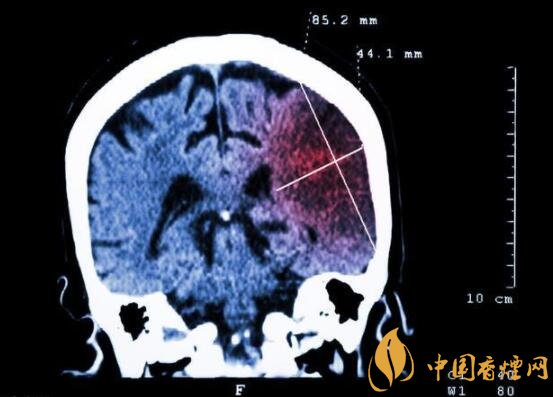

一般而言,急性腦梗塞與長(zhǎng)期吸煙有非常密切的聯(lián)系。有長(zhǎng)期煙齡遇到肢體活動(dòng)不順,做頭顱核磁共振檢查往往查出一側(cè)大腦中動(dòng)脈閉塞的可能性很高。由此可見(jiàn),吸煙確實(shí)與中風(fēng)存在一定聯(lián)系。